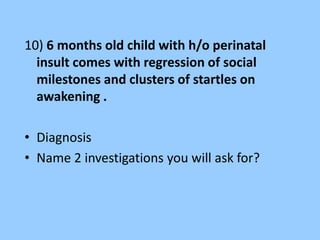

![• Station No : A term newborn who required resuscitation at

birth with a 5 minute APGAR of 5 is admitted in NICU. The

neonate had seizures in first 12 hrs of life

• Identify the findings-[1]

• What is the significance of this finding- [1/2]

• Name of the staging system other than Sarnat and Sarnat and

give its component- [1]](https://image.slidesharecdn.com/eeg-141015043102-conversion-gate01/85/Eeg-in-pediatric-DNB-PEDIATRIC-72-320.jpg)